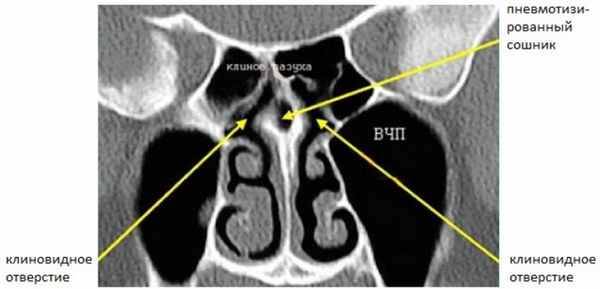

Задний ОМК (Рис. 3) расположен в сфеноэтмоидальном кармане, дренирует задние решетчатые ячейки и клиновидные пазухи.

Рисунок 3. КТ полости носа. Сошник разделяет два отверстия клиновидных пазух, которые расположены в сфеноэтмоидальном кармане. Сошник пневматизирован (норма).